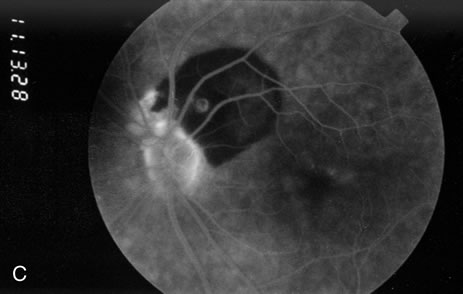

Because of rapid blood flow through retinal arterial macroaneurysms, they typically fill quickly in the early phase of the fluorescein angiogram. In the mid- and late-phases of the angiogram, the macroaneurysm tends to leak to varying degrees, depending on its perfusion and endothelial integrity (Fig. 3C). If there is subretinal fluid surrounding the aneurysm, there may be pooling of dye into the subretinal space. In some cases, a characteristic Z-shaped kink may be identified at the site of the aneurysm.

Perfusion abnormalities caused by the macroaneurysm cause changes in the surrounding retinal vasculature as well, and this is best visualized on fluorescein angiography (Fig. 3B). Ischemia from stagnation of blood flow results in capillary telangiectasis, microaneurysm formation, and capillary nonperfusion.

Some or all of these angiographic features may be obscured by blood or lipid exudation from the aneurysm. If blood collects in front of the retinal vessels (vitreous hemorrhage, preretinal hemorrhage, subinternal limiting membrane hemorrhage, or intraretinal hemorrhage), then blockage of hyperfluorescence may be partial or complete. Subretinal blood blocks hyperfluorescence from the choroid but not the retinal circulation, resulting in dramatically distinct retinal vessels against a dark background (Fig. 3B,C). Lipid exudation and retinal edema may cause partial blockage of hyperfluorescence.